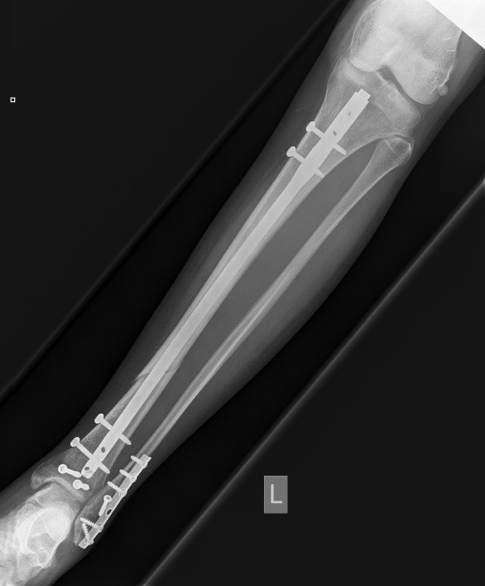

Operative Schwerpunkte

- Knorpelchirurgie mit Knorpelzüchtung oder Mosaikplastik (Einsetzten von Knorpelknochenzylinder)

- Knie- und Hüftgelenksprothesen (Gelenksersatz)

- Wiederherstellung der Gelenksfläche bei einer Fraktur (Knochenbruch)

Sonstige Operationen:

- Fraktur (Knochenbruch)

- Metallentfernung